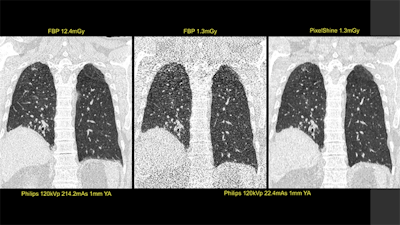

First image: Standard, high-dose CT at 12.4 mGy. Second image: Ultralowdose CT at 1.3 mGy. Third image: AI-enhanced ultralow-dose CT at 1.3 mGy. Diagnostic image quality between the first and third images was rated as comparable by independent radiologists, despite a significant dose reduction of 11.1 mGy. The second image is noisy and nondiagnostic. Image courtesy of Algomedica and Dr. Hugh Harvey, Kheiron Medical.At its booth, GE Healthcare is demonstrating software applications and "smart" devices built on Edison, its AI platform that ties together existing AI partnerships and products.